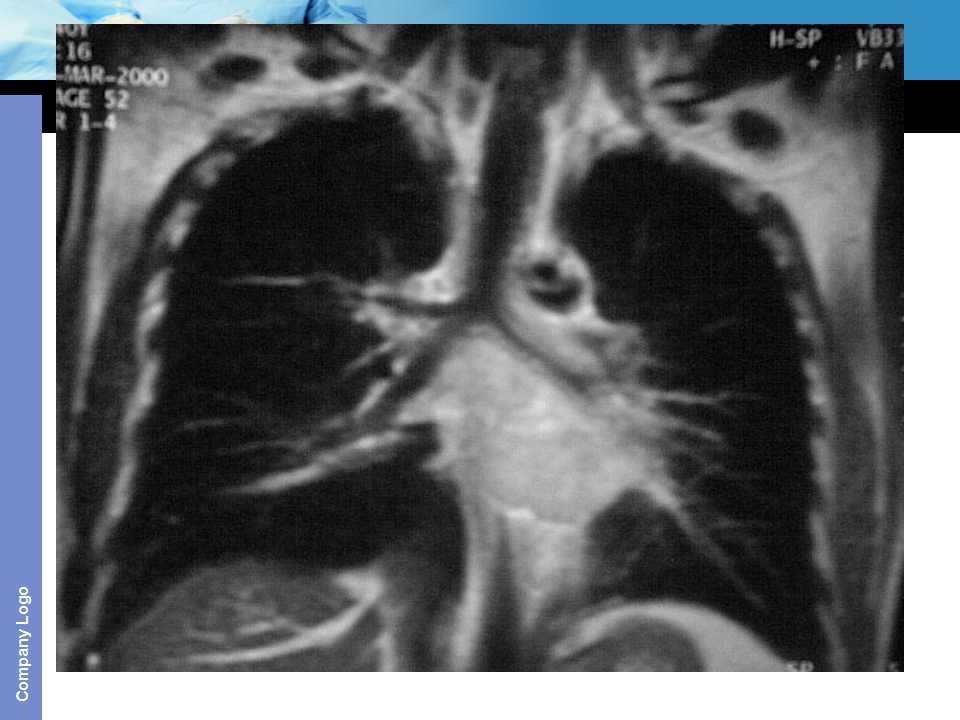

肺癌影像诊断